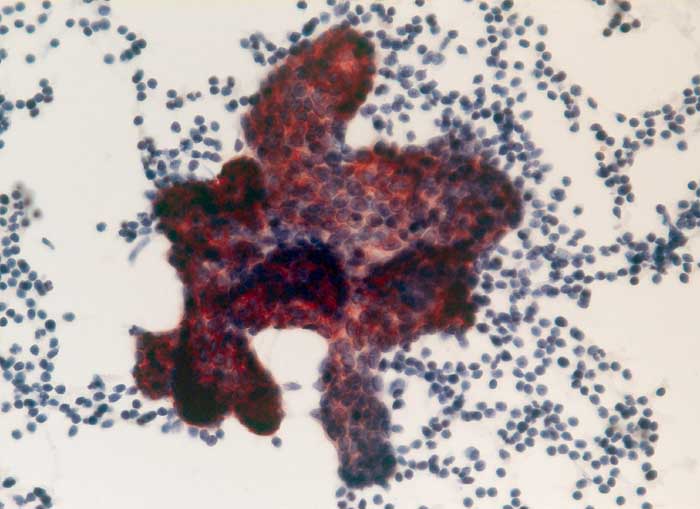

Maligner Pleuraerguss: Papilläres Nierenzellkarzin

Die papilliformen Verbände des papillären Nierenzellkarzinoms können mit pseudopapillären Verbänden reaktiver Mesothelien verwechselt werden. Die Positivität für BerEP-4 und die Negativität für den Mesothelmarker Calretinin bestätigen die Karzinomdiagnose.